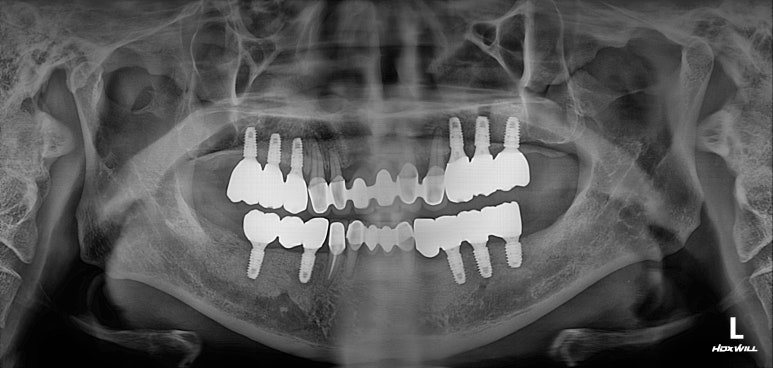

모든 최종 보철물을 연결하고 나서 치과용 파노라마 사진입니다.

정말 깔끔하게 제작된 것을 보시 수 있을겁니다.

'미적 기준'은 보편적인 측면이 있습니다. 뭔가 나란하고 비율이 대칭인 임플란트는, 잘 모르는 사람이 봐도 잘 되었구나~~ 라고 생각하게 만들어주죠 ^^

제가 가진 수술 경험을 비롯한 노하우와, 오스템 임플란트의 네비게이션 임플란트 시스템이 합작해낸 결과물!